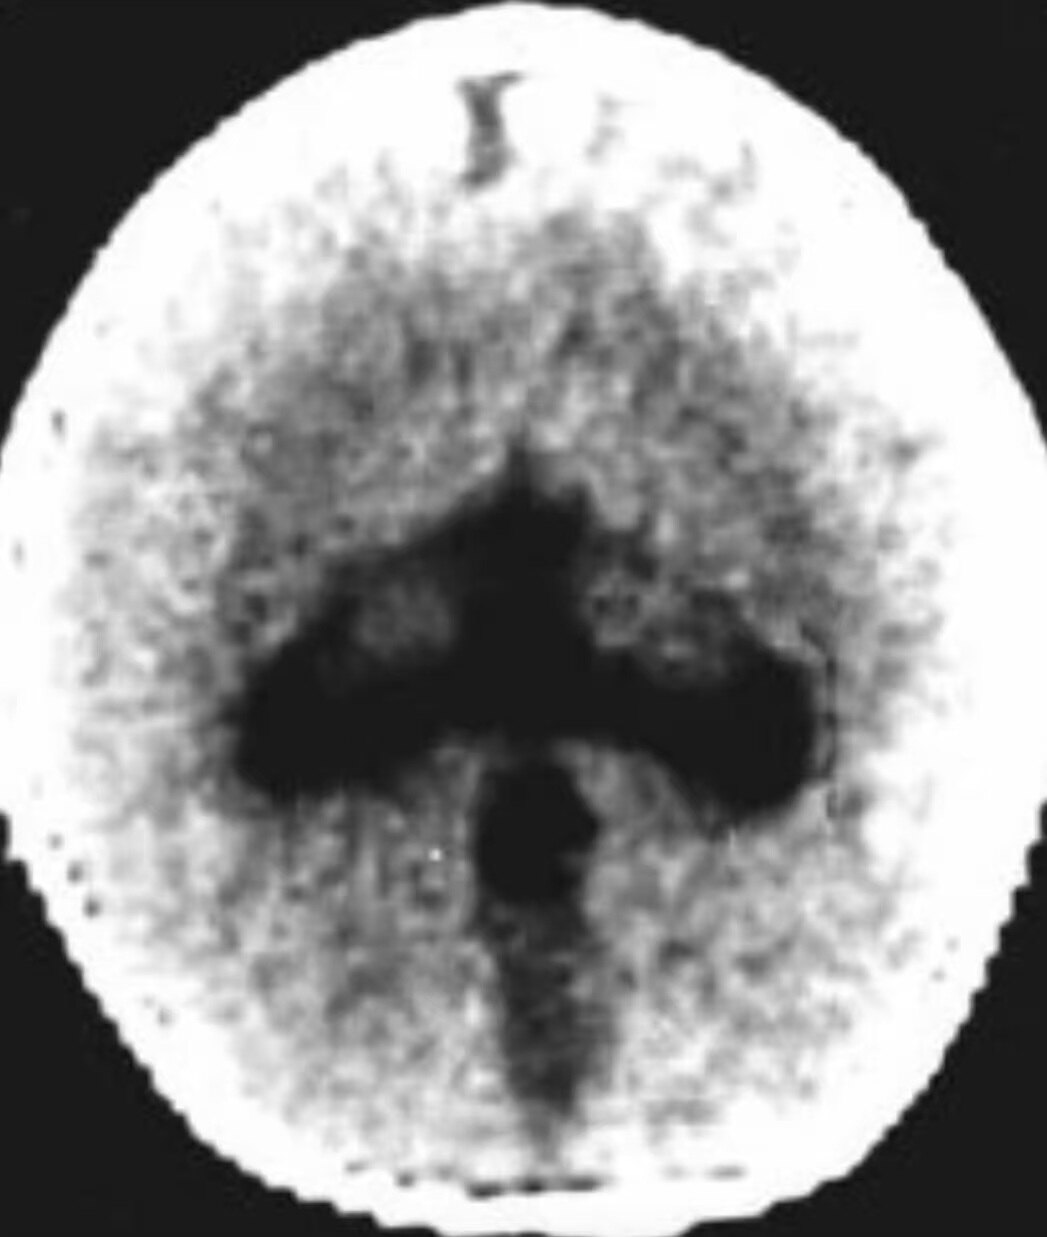

1、无脑叶型:无大脑半球,仅有一层菲薄的原始皮质围绕单一扩大的脑室,第三脑室位于单脑室下方,第四脑室正常。MRI可显示半球间裂与大脑镰完全缺如,单侧无脑叶常呈盾形,胼胝体缺如,鞍上单脑室马靴形,第三脑室缺如等。此型最严重。